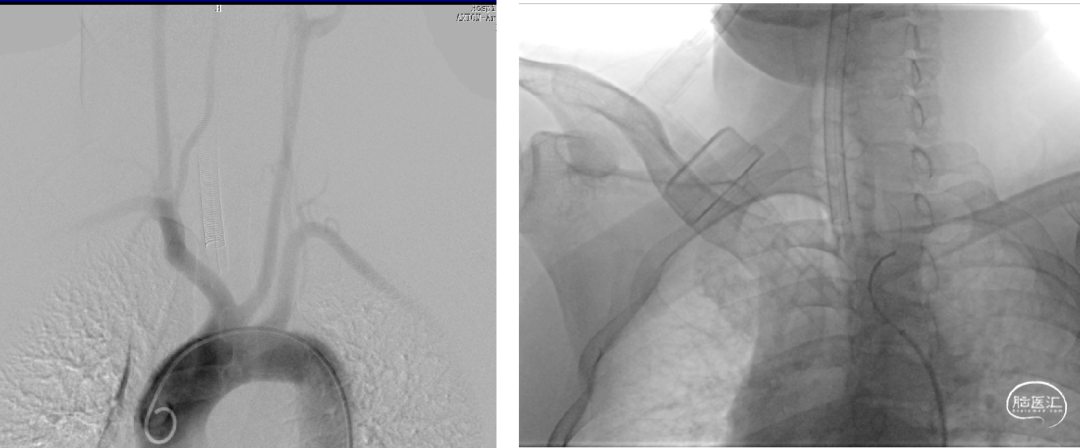

手术规划:FD+弹簧圈

FRED 3.0x14/19

术后CT